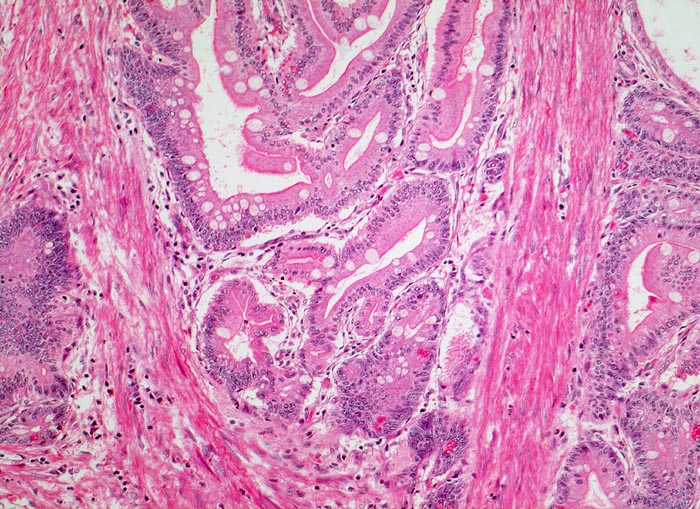

AP/ Peutz-Jeghers Polyp, Dünndarm

Peutz-Jeghers Polyp, Dünndarm

Jejunum